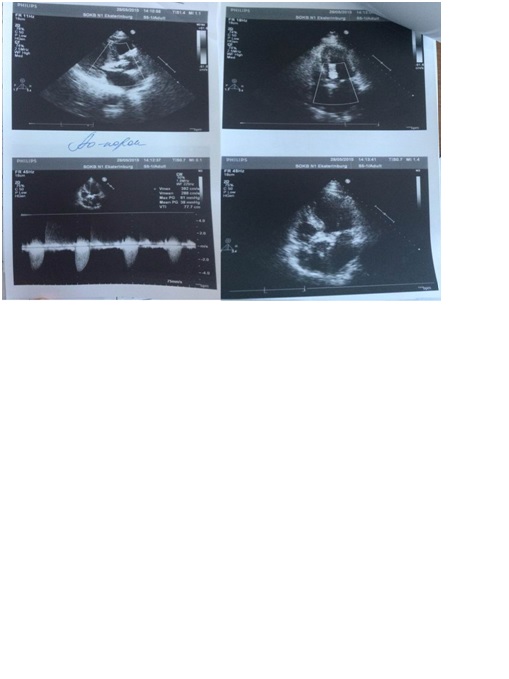

Увеличение продолжительности жизни пациентов после комплексной терапии рака молочной железы сопровождается ростом отдаленной постлучевой патологии сердца. Несвоевременная диагностика и коррекция этих осложнений приводит к ухудшению качества жизни пациентов и увеличивает риск сердечной смертности. Представлен клинический случай развития порока аортального клапана в отдаленном периоде после применения лучевой терапии у пациентки с левосторонней локализацией рака молочной железы.

Жданова И.В., Кузнецова Е.В., Михайлов А.В., Иофин А.И., Быков А.Н., Зиятдинов Д.Ж. ЛУЧЕВОЕ ПОРАЖЕНИЕ КЛАПАННОГО АППАРАТА СЕРДЦА. Комплексные проблемы сердечно-сосудистых заболеваний. 2017;(1). https://doi.org/10.17802/2306-1278-2017-1-